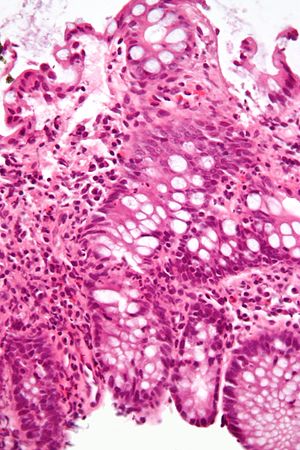

Cryptitis. (WC)

Crypt abscess. (WC)